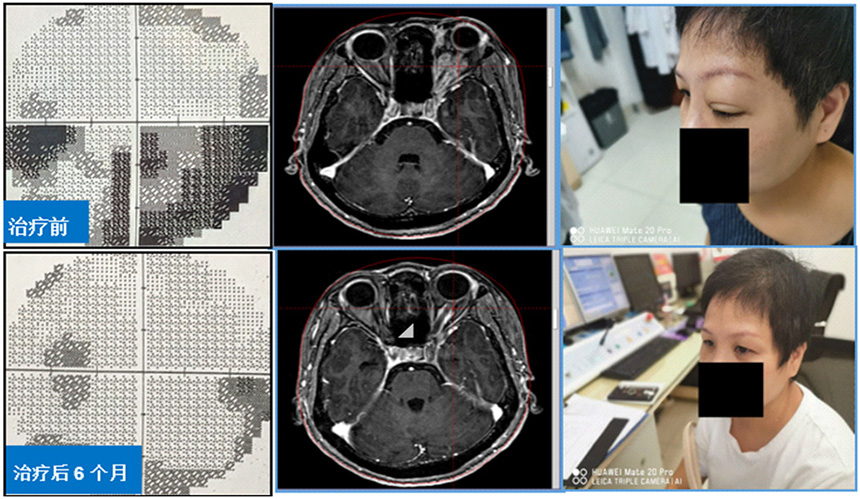

1、伽玛刀联合Ommaya囊穿刺引流术治疗巨大囊性脑转移瘤。穿刺引流可迅速改善占位效应,减少神经功能损害,结合伽玛刀治疗,提高病灶的局控率,当囊性病灶位于脑干等重要功能部位时,治疗效果更加明显。2018年12月,我们在上海脑转移瘤高峰论坛分享了此项经验。

3、伽玛刀治疗眶内球后占位,保全视力视野、改善突眼症状。球后占位患者常伴有突眼、视力下降及视野缺损,伽玛刀分割治疗可快速缓解突眼症状,减轻视神经压迫,再逐步“吃掉”残余肿瘤。该方法是眶内球后占位最有效的治疗手段之一。